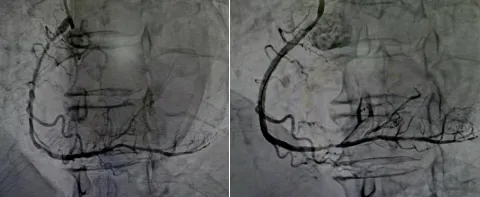

72岁的王先生因反复胸痛、活动后气促入院。冠脉造影显示,其右冠慢性重度狭窄,病变部位伴有弥漫性、浅表性重度钙化。这种钙化质地坚硬,像一层厚厚的“铠甲”包裹着血管壁,常规球囊根本无法通过或扩张。

面对这块“硬骨头”,团队决定启用旋磨技术。手术中,医生送入一枚直径仅1.5毫米的旋磨头,以每分钟16万转的高速进行精细旋磨。这个被称为“金刚钻”的微型磨头,像一位精准的“雕刻师”,将堵塞血管的坚硬钙化斑块一点点打磨成比红细胞还小的微粒,随血流排出体外。

数次旋磨后,坚硬的钙化环被成功“瓦解”,血管通道顺利打开。在血管内超声(IVUS)的精准指导下,医生顺利植入药物支架。术后造影显示,支架膨胀充分、贴壁良好,血流恢复通畅,患者症状即刻缓解。